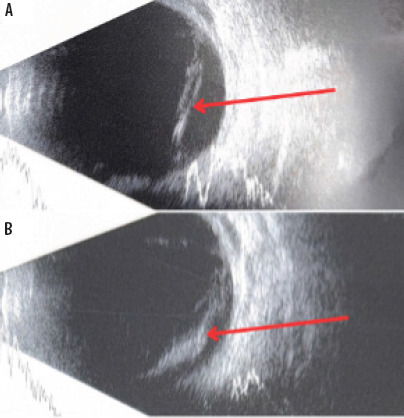

Examination of the anterior segment of the eye revealed no abnormalities in the cornea, a clear anterior chamber with no signs of Tyndall effect, a transparent lens, and preserved visibility of the fundus. Fundoscopic examination revealed the optic disc (n. II) with clear borders, the macula with a reflex, vitreous hemorrhage, a full-thickness wound of the eye wall at 10 o’clock surrounded by small hemorrhages, local retinal detachment, and hemorrhagic opacities in the nasal quadrants hindering the assessment of the retina (Figure 1). In the ultrasound examination of the left eyeball, a hemorrhage into the vitreous body was visualized (Figure 2).

Figure 2

A, B. Ultrasound B-scan examination of the left eye on the day of admission, vitreous hemorrage is indicated by red arrows